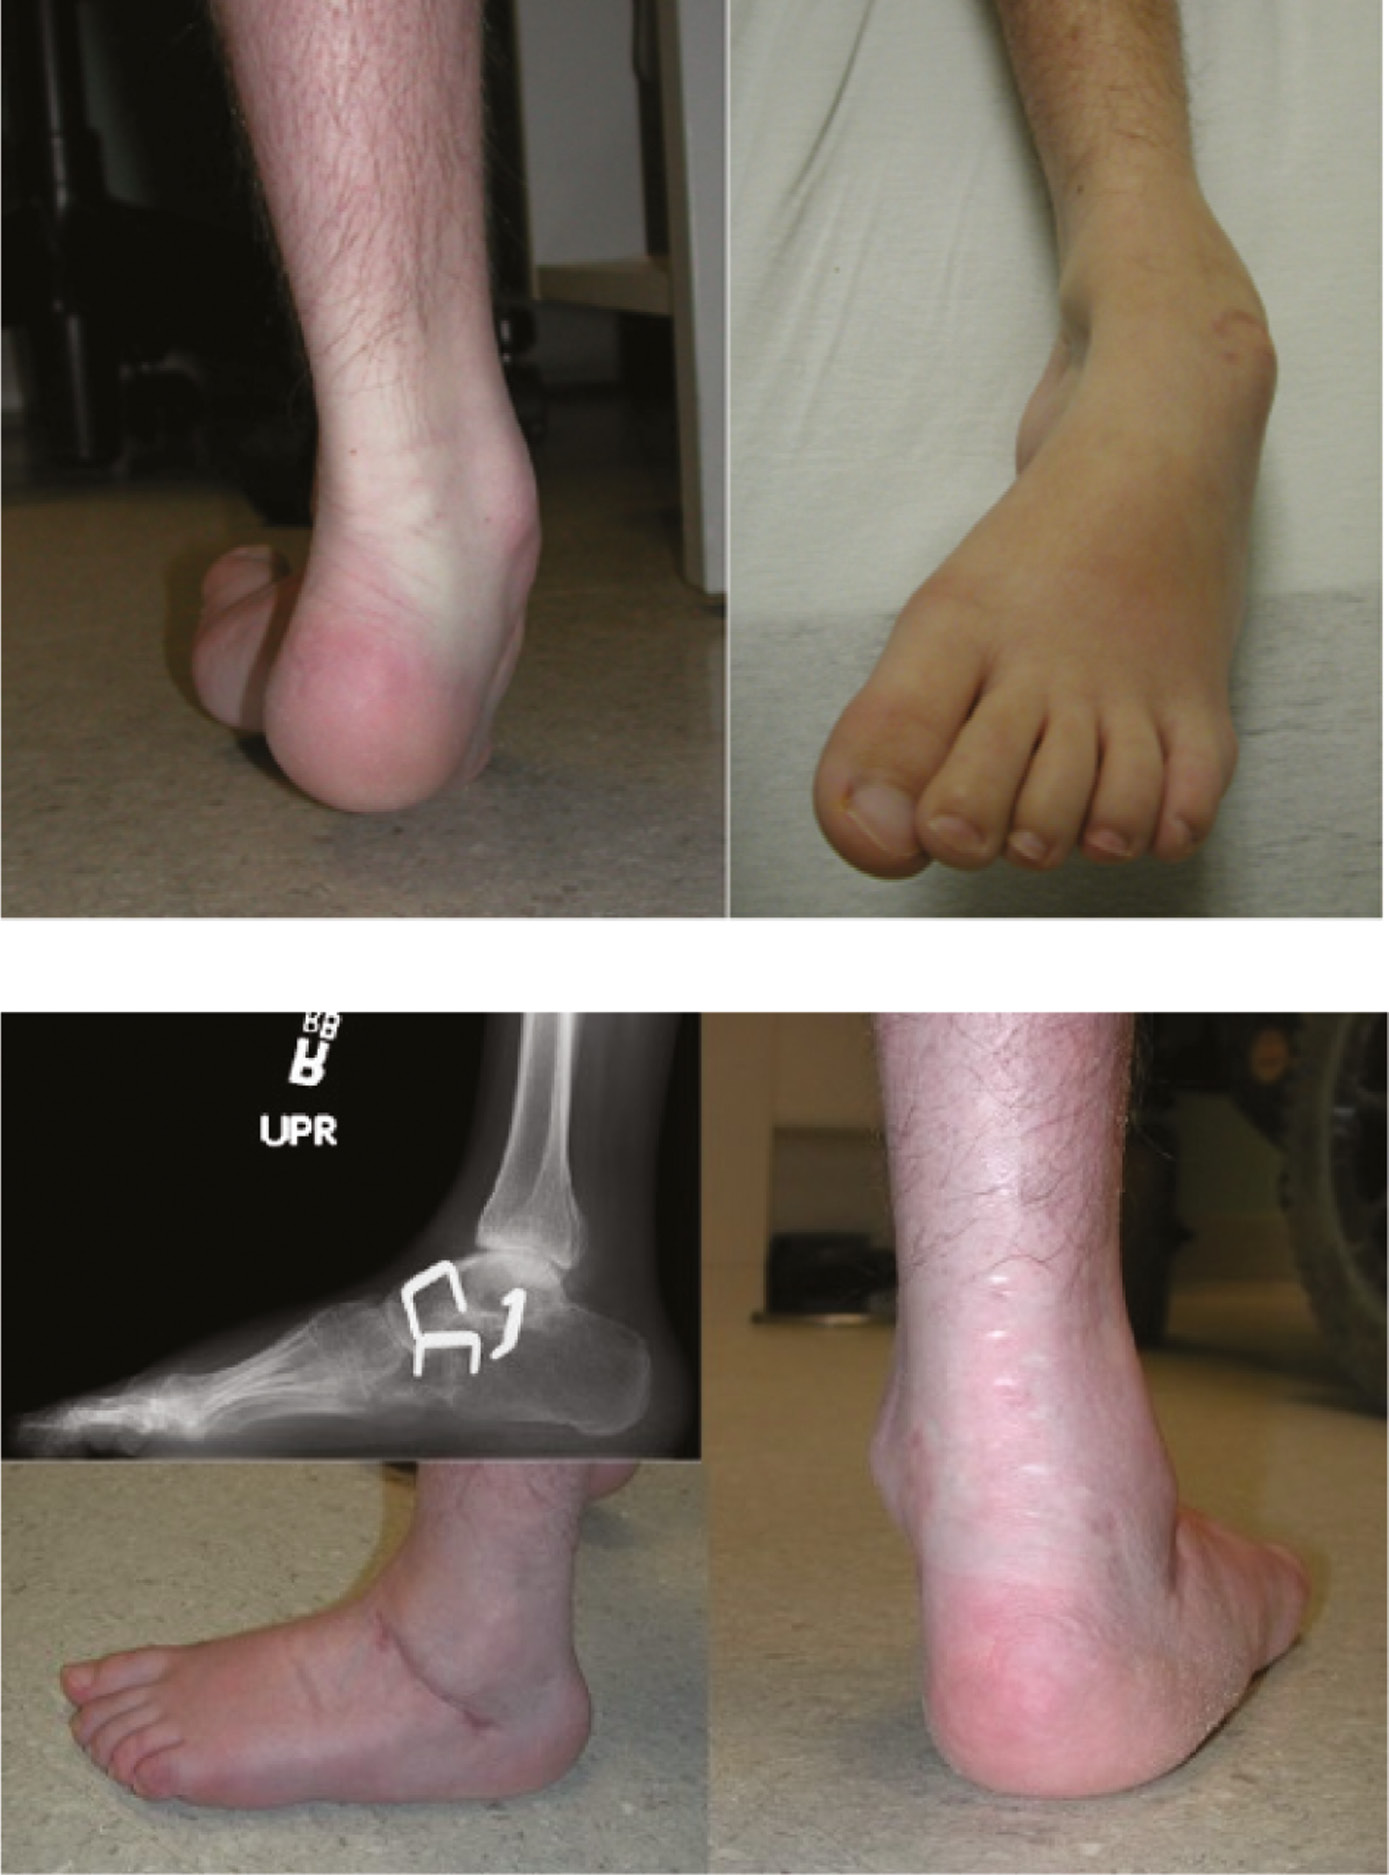

The clinician must also be aware of other less common neurologic causes of pes cavus. When unilateral cavus is seen, this may suggest the presence of a syringomyelia or tethered spinal cord (Figure 4). Peripheral nerve injury affecting the peroneal nerve may produce pes cavus as a result of lateral and anterior compartment weakness. People with cerebral palsy also tend to develop various foot deformities, with the hemiplegic type more commonly manifesting pes cavovarus.10 Patients with sacral level myelomeningocele or poliomyelitis also often demonstrate a calcaneocavus foot which is characterized by a dorsiflexed calcaneus and relative weakness of the ankle plantarflexors.11

Figure 4. This boy with a syrinx has a unilateral cavovarus foot deformity (top) with claw toes (bottom).

jposna20220035_fig4.jpg